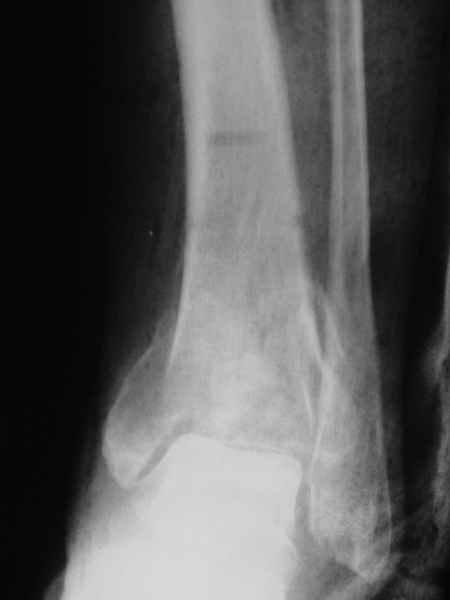

Nail arthrodesis for failed pilon fracture is good solution.

My example